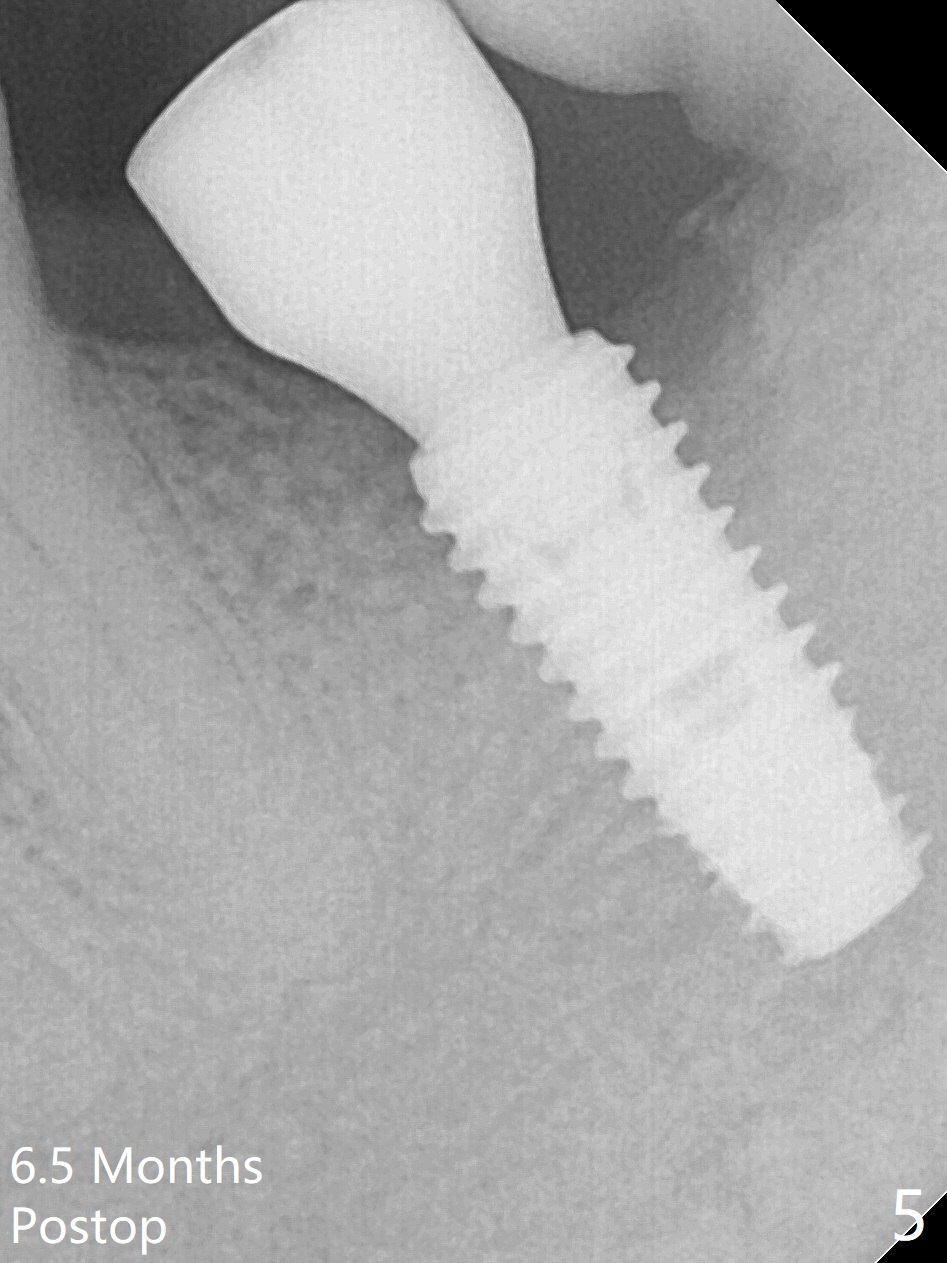

It is difficult to identify the Inferior Alveolar Canal when the initial osteotomy depth is 11.5 mm (Fig.2). Following sequential osteotomy (last drills 4.5x11.5 and 4x13 mm), a 5x11.5 mm implant is placed with >50 Ncm (Fig.3,4). Later the implant is placed .5 mm deeper with placement of a 6.5x4(4) mm abutment and autogenous bone lingually, in which ~.5 mm implant is uncovered. There is mild bone loss distal 6.5 months postop (Fig.5). Before cementation, the crown at #29 becomes loose. The abutment screw needs retightening 6 months post cementation. Six months post retightening, the abutment screw is loose at #14.